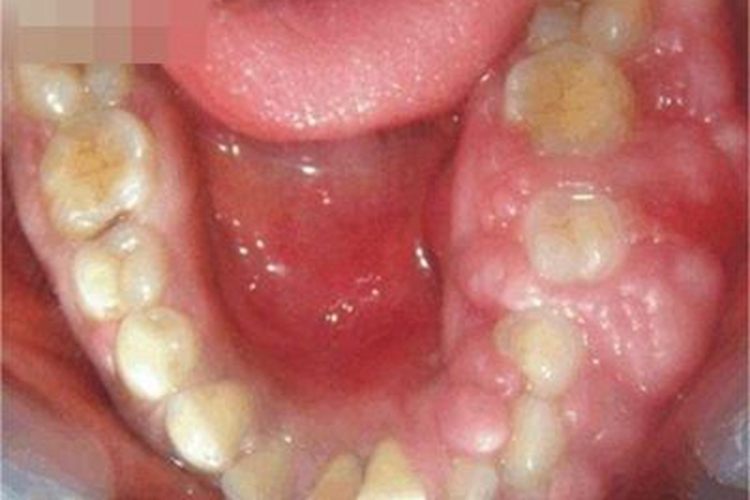

牙龈瘤可表现为下牙龈明显肿大、组织肥厚,牙龈严重变形。

牙龈瘤可表现为下牙龈明显肿大、组织肥厚,牙龈严重变形,失去原有的形态,其内的牙齿被牙龈组织包裹,因挤压而出现牙列不齐,咀嚼功能受到明显影响。